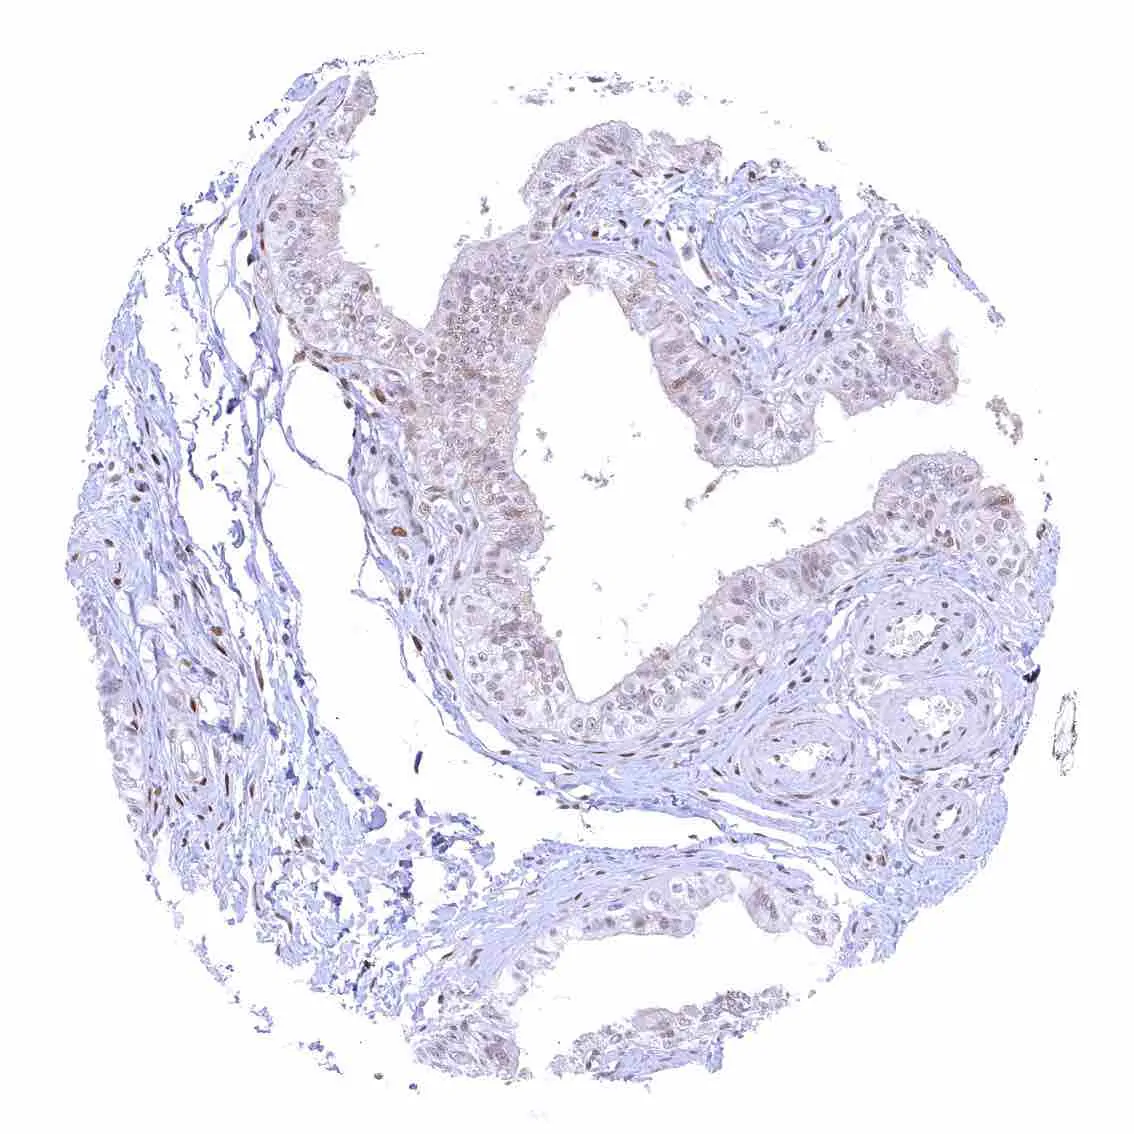

Breast – Moderate to strong nuclear p27 positivity of a large fraction of glandular epithelial cells.